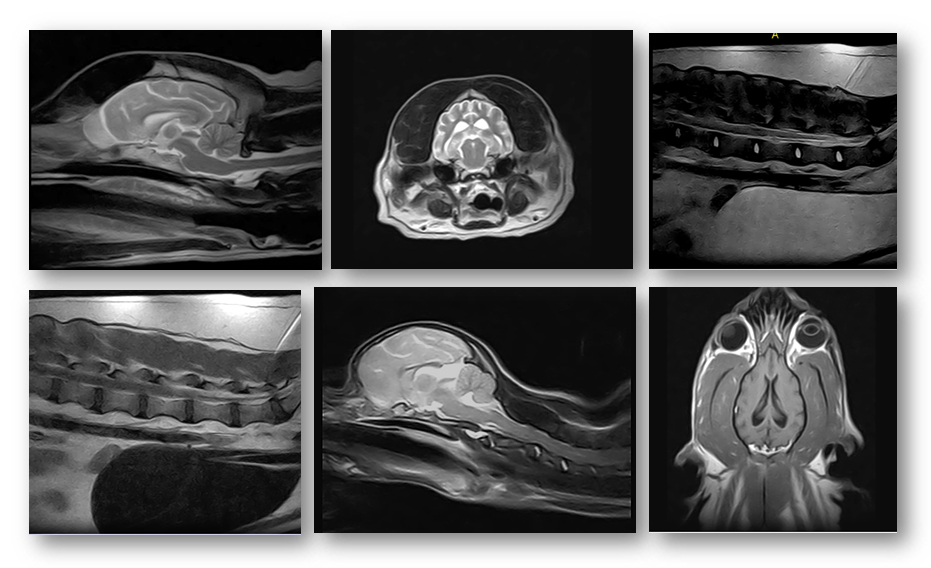

University Veterinary Specialists continues to advance veterinary medicine in Western Pennsylvania with its debut of the first animal-specific mid-field strength MRI in the United States. The Magnus AIP-Vet MRI is only the second of its kind with the first installed in Perth, Australia. A great balance of high quality imaging and affordability.

Animal hospitals providing MRI imaging commonly use pre-owned human MRI machines. The brand new Magnus AIP-Vet MRI is designed exclusively for companion animals using veterinary-specific software.

“The advancements that were utilized when building this MRI are incredible. We are producing images comparable to a high-field machine, but with better affordability and faster, thus safer, scans. The machine is specifically designed for use with pets, and even the table has a special shape to accommodate veterinary patients. There are many upsides to having an MRI performed with this unit,” said Chief Medical Officer Dr. Dimitri Brown.

The Magnus MRI uses state-of-the-art electronics and fiber optic cabling to decrease scan times, which leads to a shorter amount of time that an animal needs to be anesthetized. And at only 50dB, the machine is significantly quieter than a high-field MRI, which can reach decibel levels of up to 120 – or the equivalent of being at a live rock concert.

MRI scans from the Magnus MRI at University Veterinary Specialists are priced at just $1,295; roughly half of what a high-field MRI scan costs, with comparable imaging.